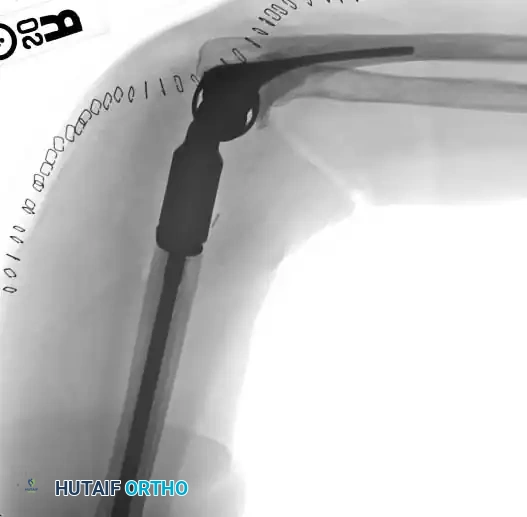

While proximal humeral resections dominate shoulder oncology, tumors extending into the humeral diaphysis or distal humerus require equally complex limb salvage strategies. Total humeral replacement or distal humeral megaprostheses are viable options when the radial nerve can be preserved or grafted.

Intraoperative Imaging and Margin Assessment

Continuous intraoperative assessment using fluoroscopy and frozen section pathology is mandatory. The following images demonstrate various stages of complex upper extremity resections, allograft preparations, and prosthetic implantations across the humerus and elbow joint.